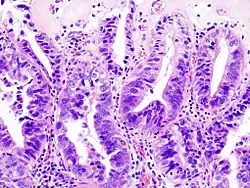

Rak pęcherzyka żółciowego (łac. adenocarcinoma vesicae felleae, ang. gallbladder cancer) – choroba nowotworowa pęcherzyka żółciowego, powstająca wskutek nowotworowej transformacji nabłonka gruczołowego wyścielającego światło narządu. Jest rzadkim nowotworem, źle rokującym ze względu na długo bezobjawowy przebieg.